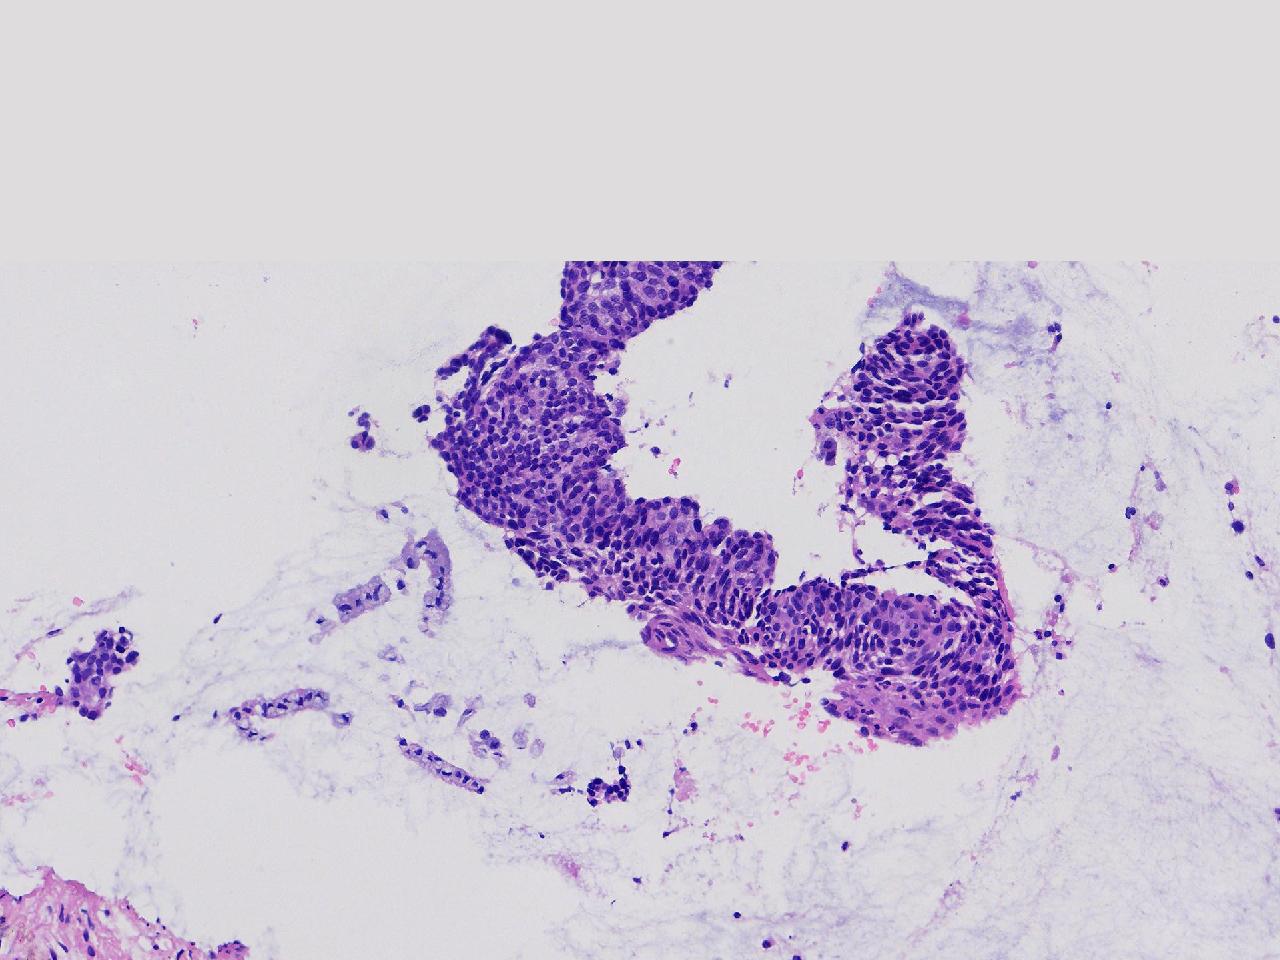

CIN2级?

女,46岁,宫颈活检。HPV16+

标本名称

宫颈活检

大体所见

宫颈多点活检。

CIN2...